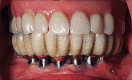

Figure 2

(a and b) Single midline implant with a ball attachment to retain a mandibular overdenture